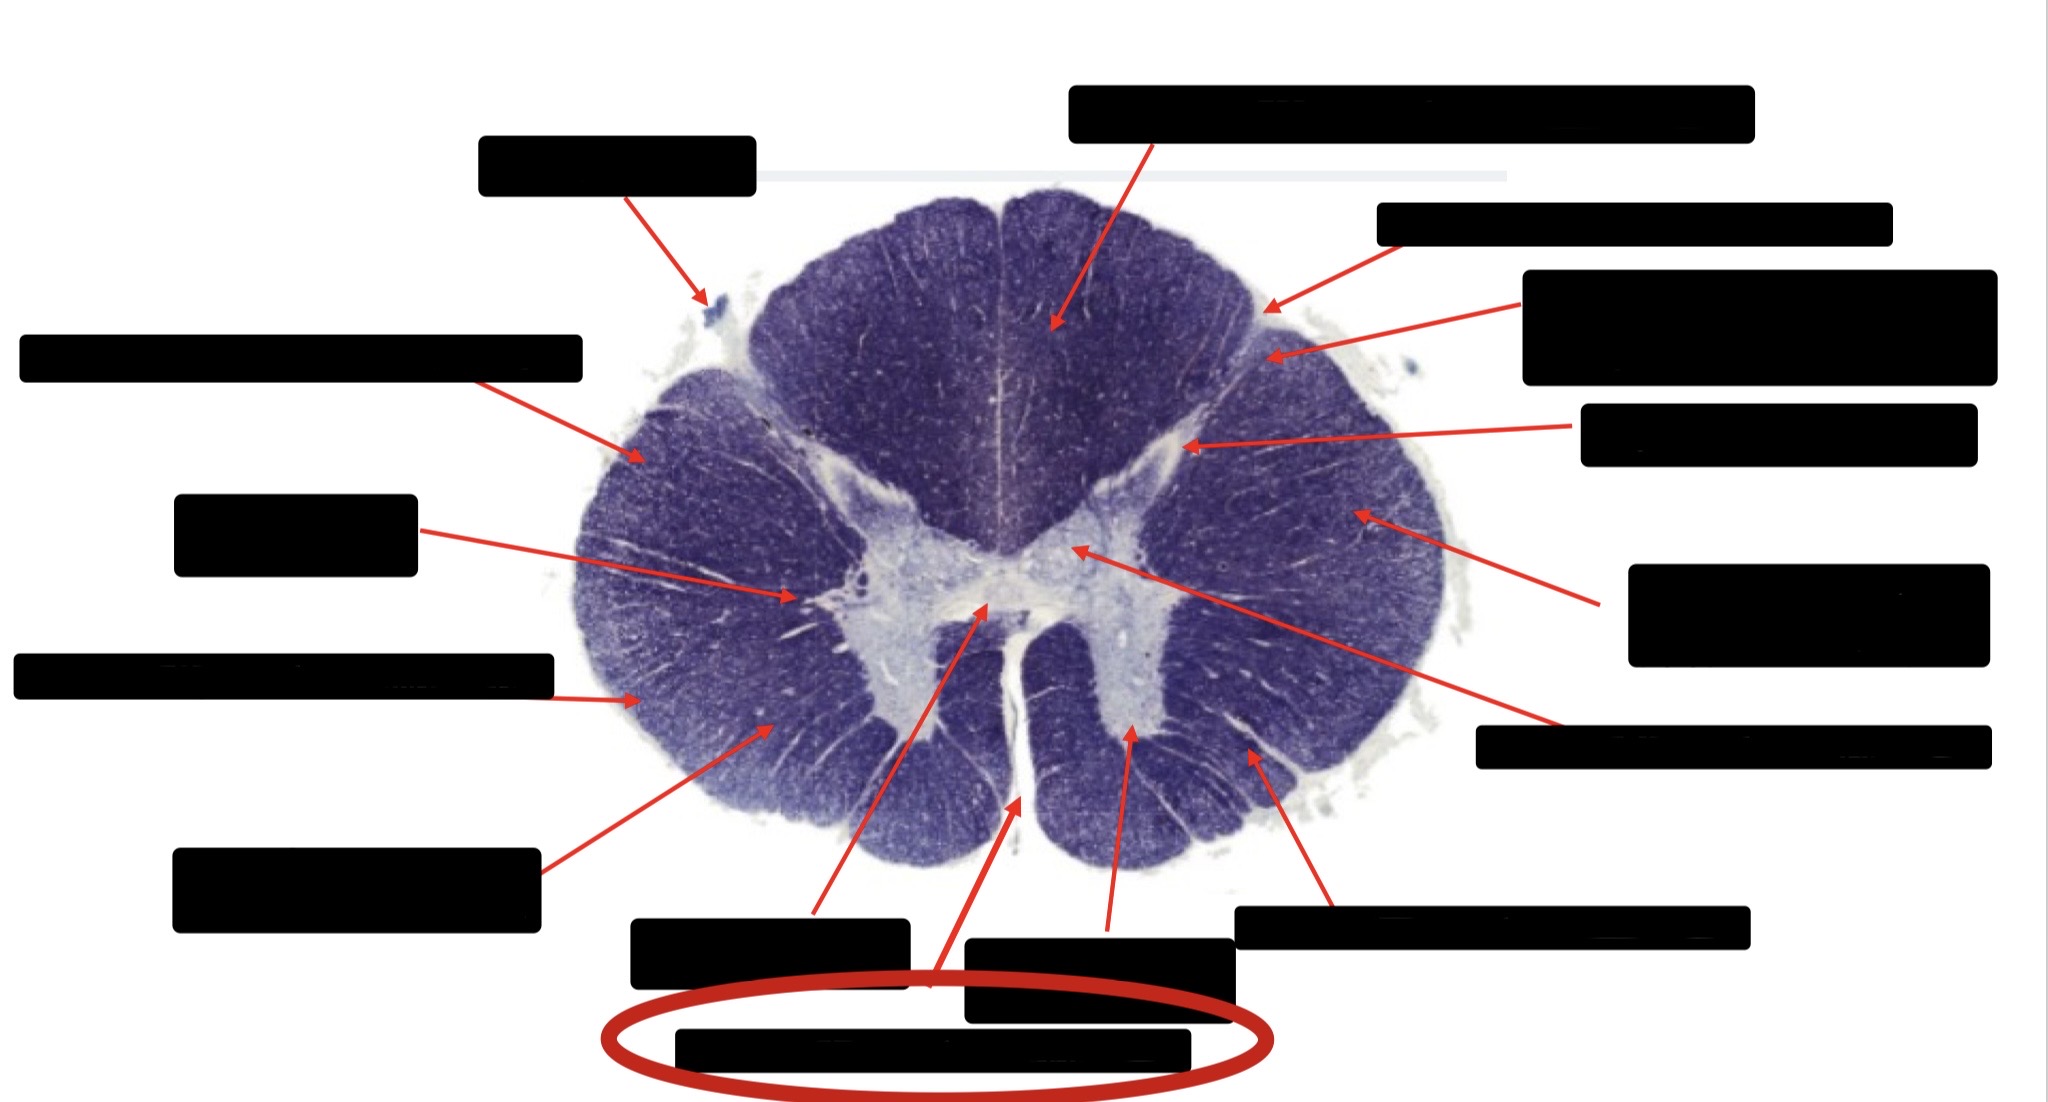

Anterior Spinal Artery

Denticulate Ligament

Ventral Root

Dorsal Root

Posterior Column Fasciculus Gracilis

Large Fiber Entry Zone

Central Canal

Dorsal Rootlet

Lissaeur’s Tract & Small Fiber Entry Zone

Substantia Gelatinosa

Lateral Corticospinal Tract

Anterior Horn Motor Neuron

Spinothalmic Tract

Anterior Horn Motor Neurons